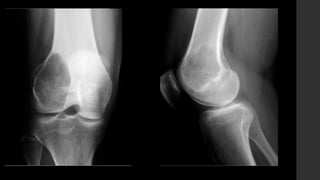

Tumor de Células Gigantes.

•También conocidos como osteoclastomas.

•Son tumores óseos relativamente comunes,

usualmente benignos que nacen de la metáfisis y se

extienden hacia la epífisis de los huesos largos.

•Representan 18 – 23% de los tumores benignos óseos

y 4 – 9.5% de todos los tumores primarios óseos.

• Se localizan en huesos largos y sólo en núcleos de osificación cerrados, cercanos a

la superficie articular (84 – 99% <1cm).

• Son lesiones bien definidas excéntricas con margen no esclerótico.

• RX y TC 

 Zona de transición delgada sin esclerosis periférica.

 La corteza adyacente está adelgazada, expandida o deficiente.

 Reacción perióstica sólo en 10 - 30% de los casos.

 Puede presentar masa de tejidos blandos.

 Puede haber fracturas patológicas.

 No presentan matriz calcificada.